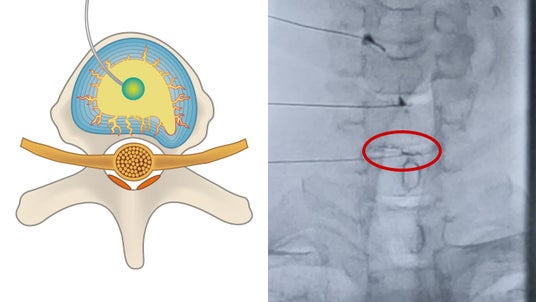

頚椎ディスクシール治療のイメージ

ディスクシール治療(The DISCSEEL(R) Procedure)は、2010年より米国テキサス州において脊椎外科専門医ケビン・パウザ医師らが研究・開発を進めてきた先進的な脊椎疾患に対する治療法です。

損傷した椎間板に直接治療薬を注入することで、椎間板の亀裂を密封し、炎症に関与する症状の改善を目的としています。

● 椎間板の「漏れ」を椎間板造影検査(アニュログラム)で特定し、直接アプローチ